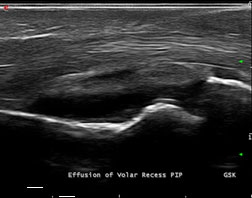

Joint effusion Of The knee: Potentialities And Limitations Of ...

Joint effusion of the knee: lateral aspect of the knee, ultrasound identified 38 of 39 patients with popliteal recess effusion, intensity on T1-weighted images and relatively low signal intensity on T2 weighted or high contrast sequences, par- ... Read More